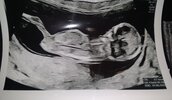

Wszystko książkowo na usg, dzidzia z USG 13+0 z OM 12+3. Ma 67.3mm. Czekam na wynik pappy, lekarz na zadzwonić do mnie. Płci nie poznałam. Dodam potem zdjęcie, bo jak dodaje to mnie z forum wywala. Co do moczu to tylko zuravit mam brać